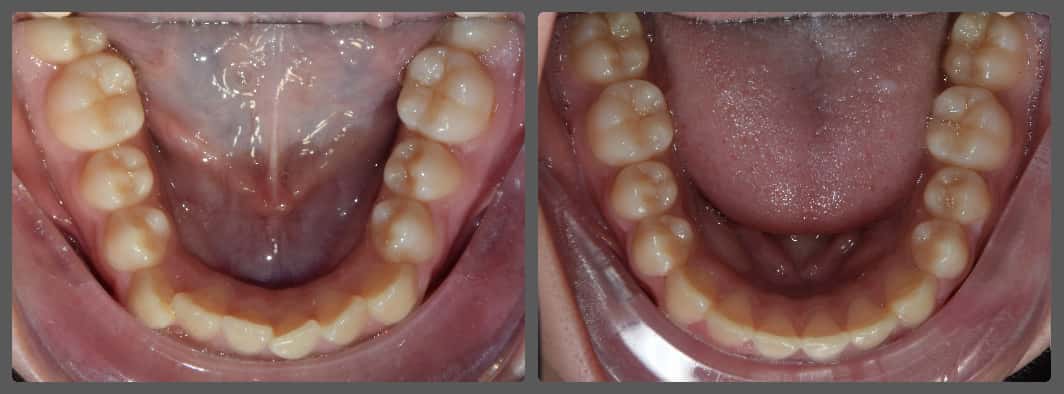

Balázs súlyos alsó torlódása miatt keresett fel magánrendelésemen. A diagnosztikus vizsgálatok során előbbin túl alsó-felső fogívszűkületet, valamint nyitott harapási hajlamot állapítottam meg. Kezelését Pitts21 alsó-felső rögzített fogszabályozó készülékkel kezdtük meg. A nyitott harapási hajlamot a hátsó fogakra helyezett harapásemelővel kontrolláltuk. A torlódott fogaknak tolórugóval és interproximális redukcióval teremtettünk helyet, és intermaxilláris gumihúzással tökéletesítettük a harapást. A fogszabályzó kezelés teljes időtartama alatt Balázs 110%-osan együttműködő volt, ezért 21 hónap alatt sikerült kiemelkedő végeredményt elérnünk.